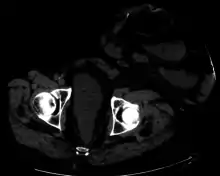

Surgical procedures that involve the creation of an artificial stoma have names that typically end with the suffix "-ostomy", and the same names are also often used to refer to the stoma thus created. For example, the word "colostomy" often refers either to an artificial anus or the procedure that creates one. Accordingly, it is not unusual for a stoma to be called an ostomy (plural ostomies), as is the norm in wound, ostomy, and continence nursing.

One well-known form of an artificial stoma is a colostomy, which is a surgically created opening in the large intestine that allows the removal of feces out of the body, bypassing the rectum, to drain into a pouch or other collection device. This surgical procedure is invoked usually as a result of and solution to disease in the GIT. The procedure involves bisecting this tube, usually between the later stage of the small intestine (ileum) and the large intestine or colon, hence colostomy, and exiting it from the body in the abdominal region. The point of exiting is what is known as the stoma.